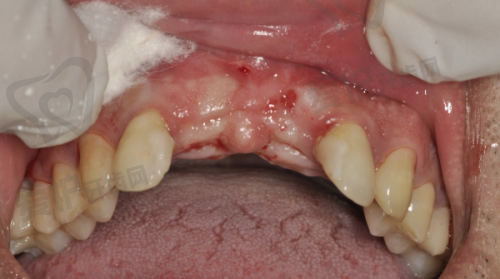

复杂病例(如骨量不足需植骨、上颌窦提升等)会增加费用,可能额外支付2000 - 6000元。因为这些复杂情况需要医生具备更高的技术水平和更丰富的经验,同时也需要使用更多的材料和设备。经验多的医生操作更精细,能够更好地应对各种复杂情况,确保种植牙的长期成效更稳定。